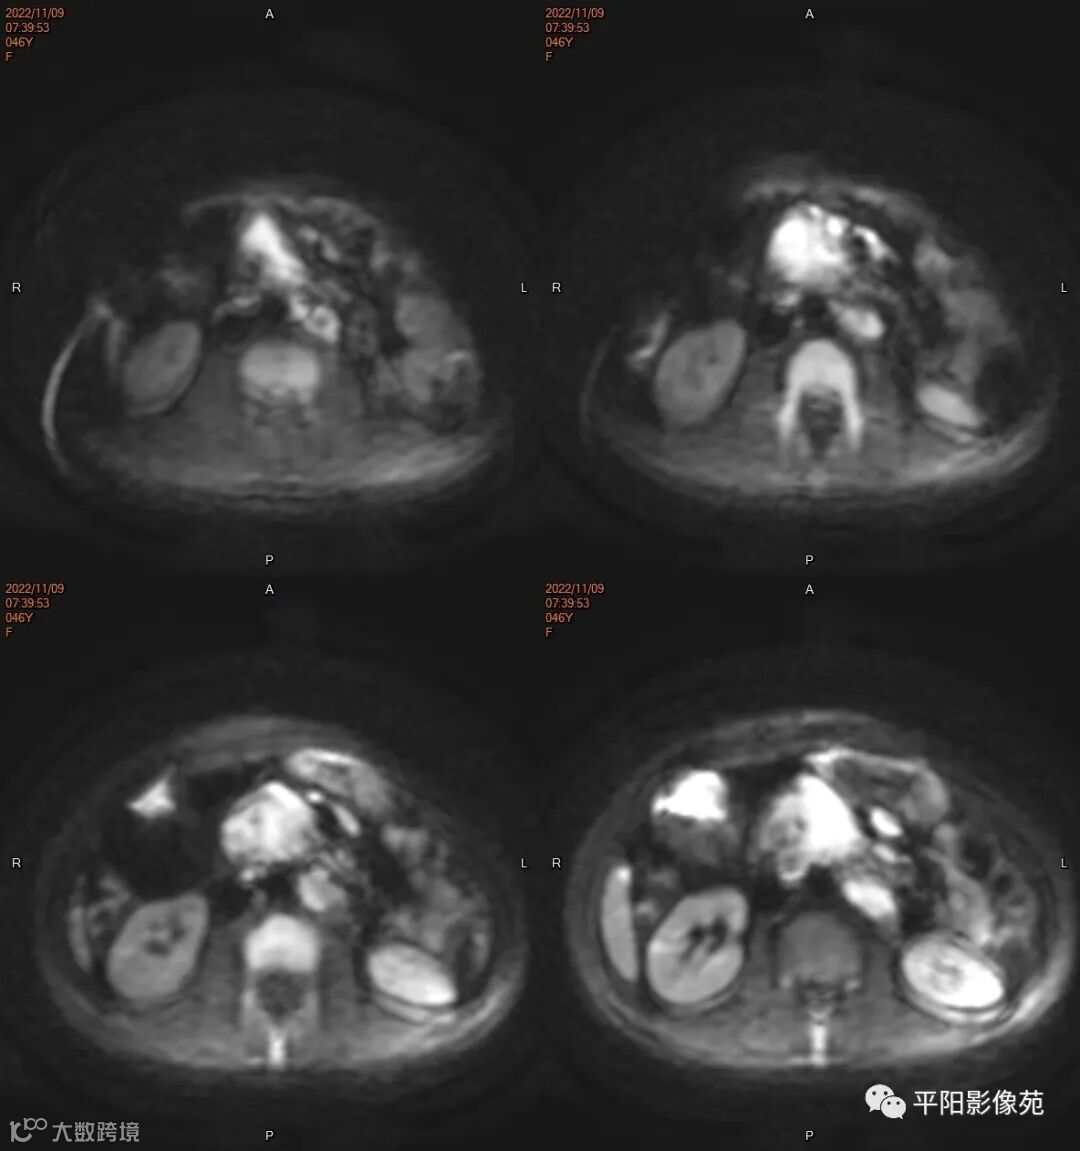

MR

影像表现: